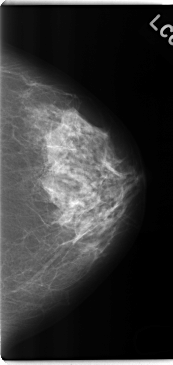

ics_version 1.0 filename C-0234-1 DATE_OF_STUDY 22 12 1994 PATIENT_AGE 40 FILM FILM_TYPE REGULAR DENSITY 2 DATE_DIGITIZED 28 4 1998 DIGITIZER LUMISYS LASER SEQUENCE LEFT_CC LINES 4736 PIXELS_PER_LINE 2240 BITS_PER_PIXEL 12 RESOLUTION 50 NON_OVERLAY LEFT_MLO LINES 4760 PIXELS_PER_LINE 2680 BITS_PER_PIXEL 12 RESOLUTION 50 NON_OVERLAY RIGHT_CC LINES 4760 PIXELS_PER_LINE 2512 BITS_PER_PIXEL 12 RESOLUTION 50 OVERLAY RIGHT_MLO LINES 4688 PIXELS_PER_LINE 2608 BITS_PER_PIXEL 12 RESOLUTION 50 OVERLAY |